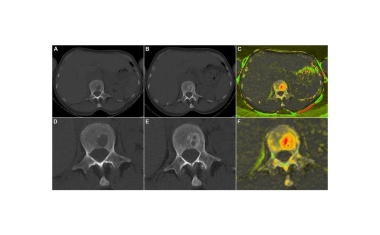

Studie vom Uniklinikum Würzburg liefert erstmals ein Maß, um die Knochenregeneration beim Multiplen Myelom zu beurteilen. Die Vermessung der Läsionsgröße ist ein verlässlicher Parameter für die Definition des Endpunktes in geplanter Folgestudie zur Bewegungstherapie.